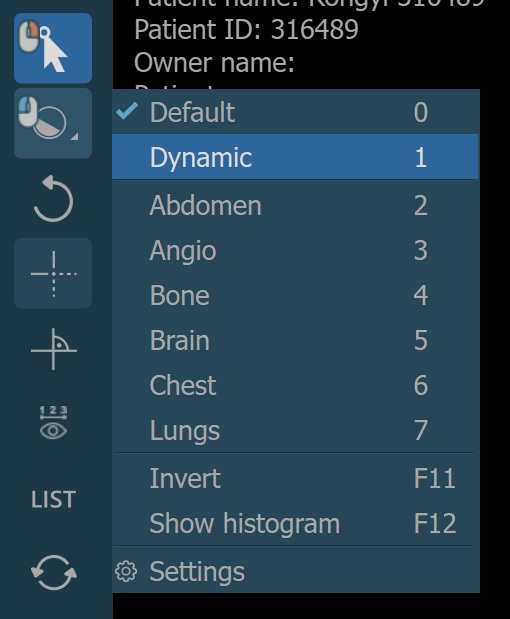

There are two different windowing modes available in the CT Viewer, Default and Dynamic. Change the active windowing mode by using the menu when selecting the Windowing tool.

The windowing presets are also available from the windowing menu when the default windowing mode is active.

Dynamic Windowing¶

The preset values for the dynamic windowing mode are represented as a percentage of the maximum determined windowing range. All of the preset values are available in the windowing menu when dynamic mode is active.

The windowing presets can also be modified directly by the CT Viewer. To open the windowing preset settings, select the Settings option from the windowing menu.